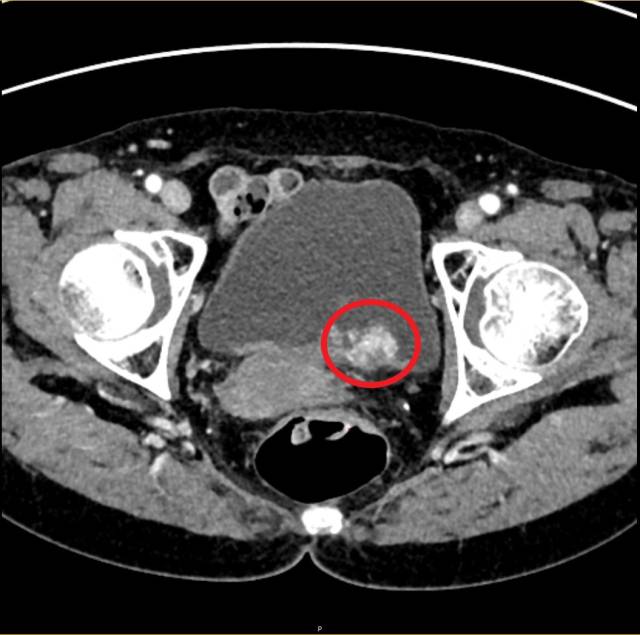

방광암의 가장 흔한 증상은 통증이 없는 혈뇨다. 방광암 환자 10명 중 9명은 혈뇨가 첫 번째 증상으로 나타난다. 소변이 명백하게 붉은색으로 보이거나 녹색으로 변할 수도 있다. 정상보다 더 자주 소변이 마렵거나 갑자기 소변이 마려운 절박뇨, 배뇨 시 통증이 발생하는 배뇨통 등의 증상을 겪기도 한다. 이는 전립선염 같은 전립선질환이나 방광염 증상과 유사하다. 만약 전립선이나 방광질환이 잘 치료되지 않는다면 방광암을 의심해보는 것이 좋다. 대개 암이 진행되면 체중감소와 통증이 나타나는데 전이 부위에 따라 증상이 달라진다. 뼈로 암이 전이되어 뼈에 통증이 생기고 신장에 물이 차는 수신증이 생기면서 옆구리 통증이 생길 수 있다. 방광암이 의심되면 먼저 컴퓨터단층촬영(CT)과 방광내시경 검사를 시행한다. 방광에 종양이 보이면 전신마취 상태에서 요도를 통한 내시경 수술로 종양 조직을 절제하고, 병리검사로 방광암을 확진하게 된다. 이 때 암세포가 저등급 혹은 고등급인지, 암조직이 방광 근육을 침범했는지 여부가 중요하다. 저등급 암은 대개 진행·전이가 드물고 임상 경과가 양호하지만 고등급 암은 진행·재발이 흔하기 때문에 보다 주의를 기울여야 한다.